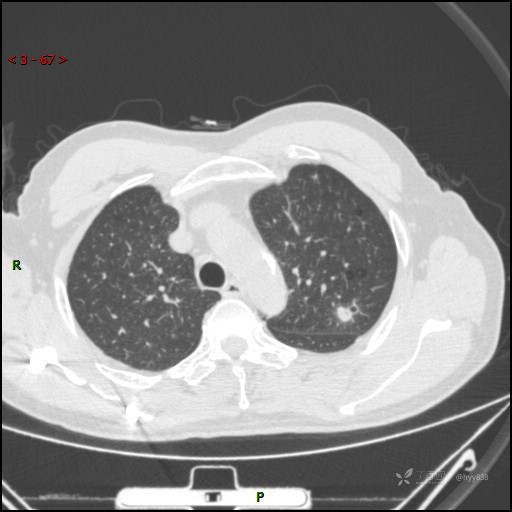

又遇恼人的肺结节,囊腔 VS 空洞 VS 空泡,欢迎讨论---结果公布~

患者年龄:61岁

主诉:发现左肺结节半月

简要病史:患者半月前因双眼翼状胬肉于我院眼科就诊行手术治疗,完善胸部CT发现左肺结节,未行特殊处理,偶有刺激性干咳,每于受凉后及饮冷水后发作,休息后可自行缓解,无发热、恶心呕吐、胸痛咯血,现为求进一步诊治,于我院就诊,门诊以“左肺结节”收入我科。 起病以来,患者食欲尚可,大小便正常,睡眠、精神可,体力、体重无明显变化。

临床诊断:肺结节

胸部CT平扫